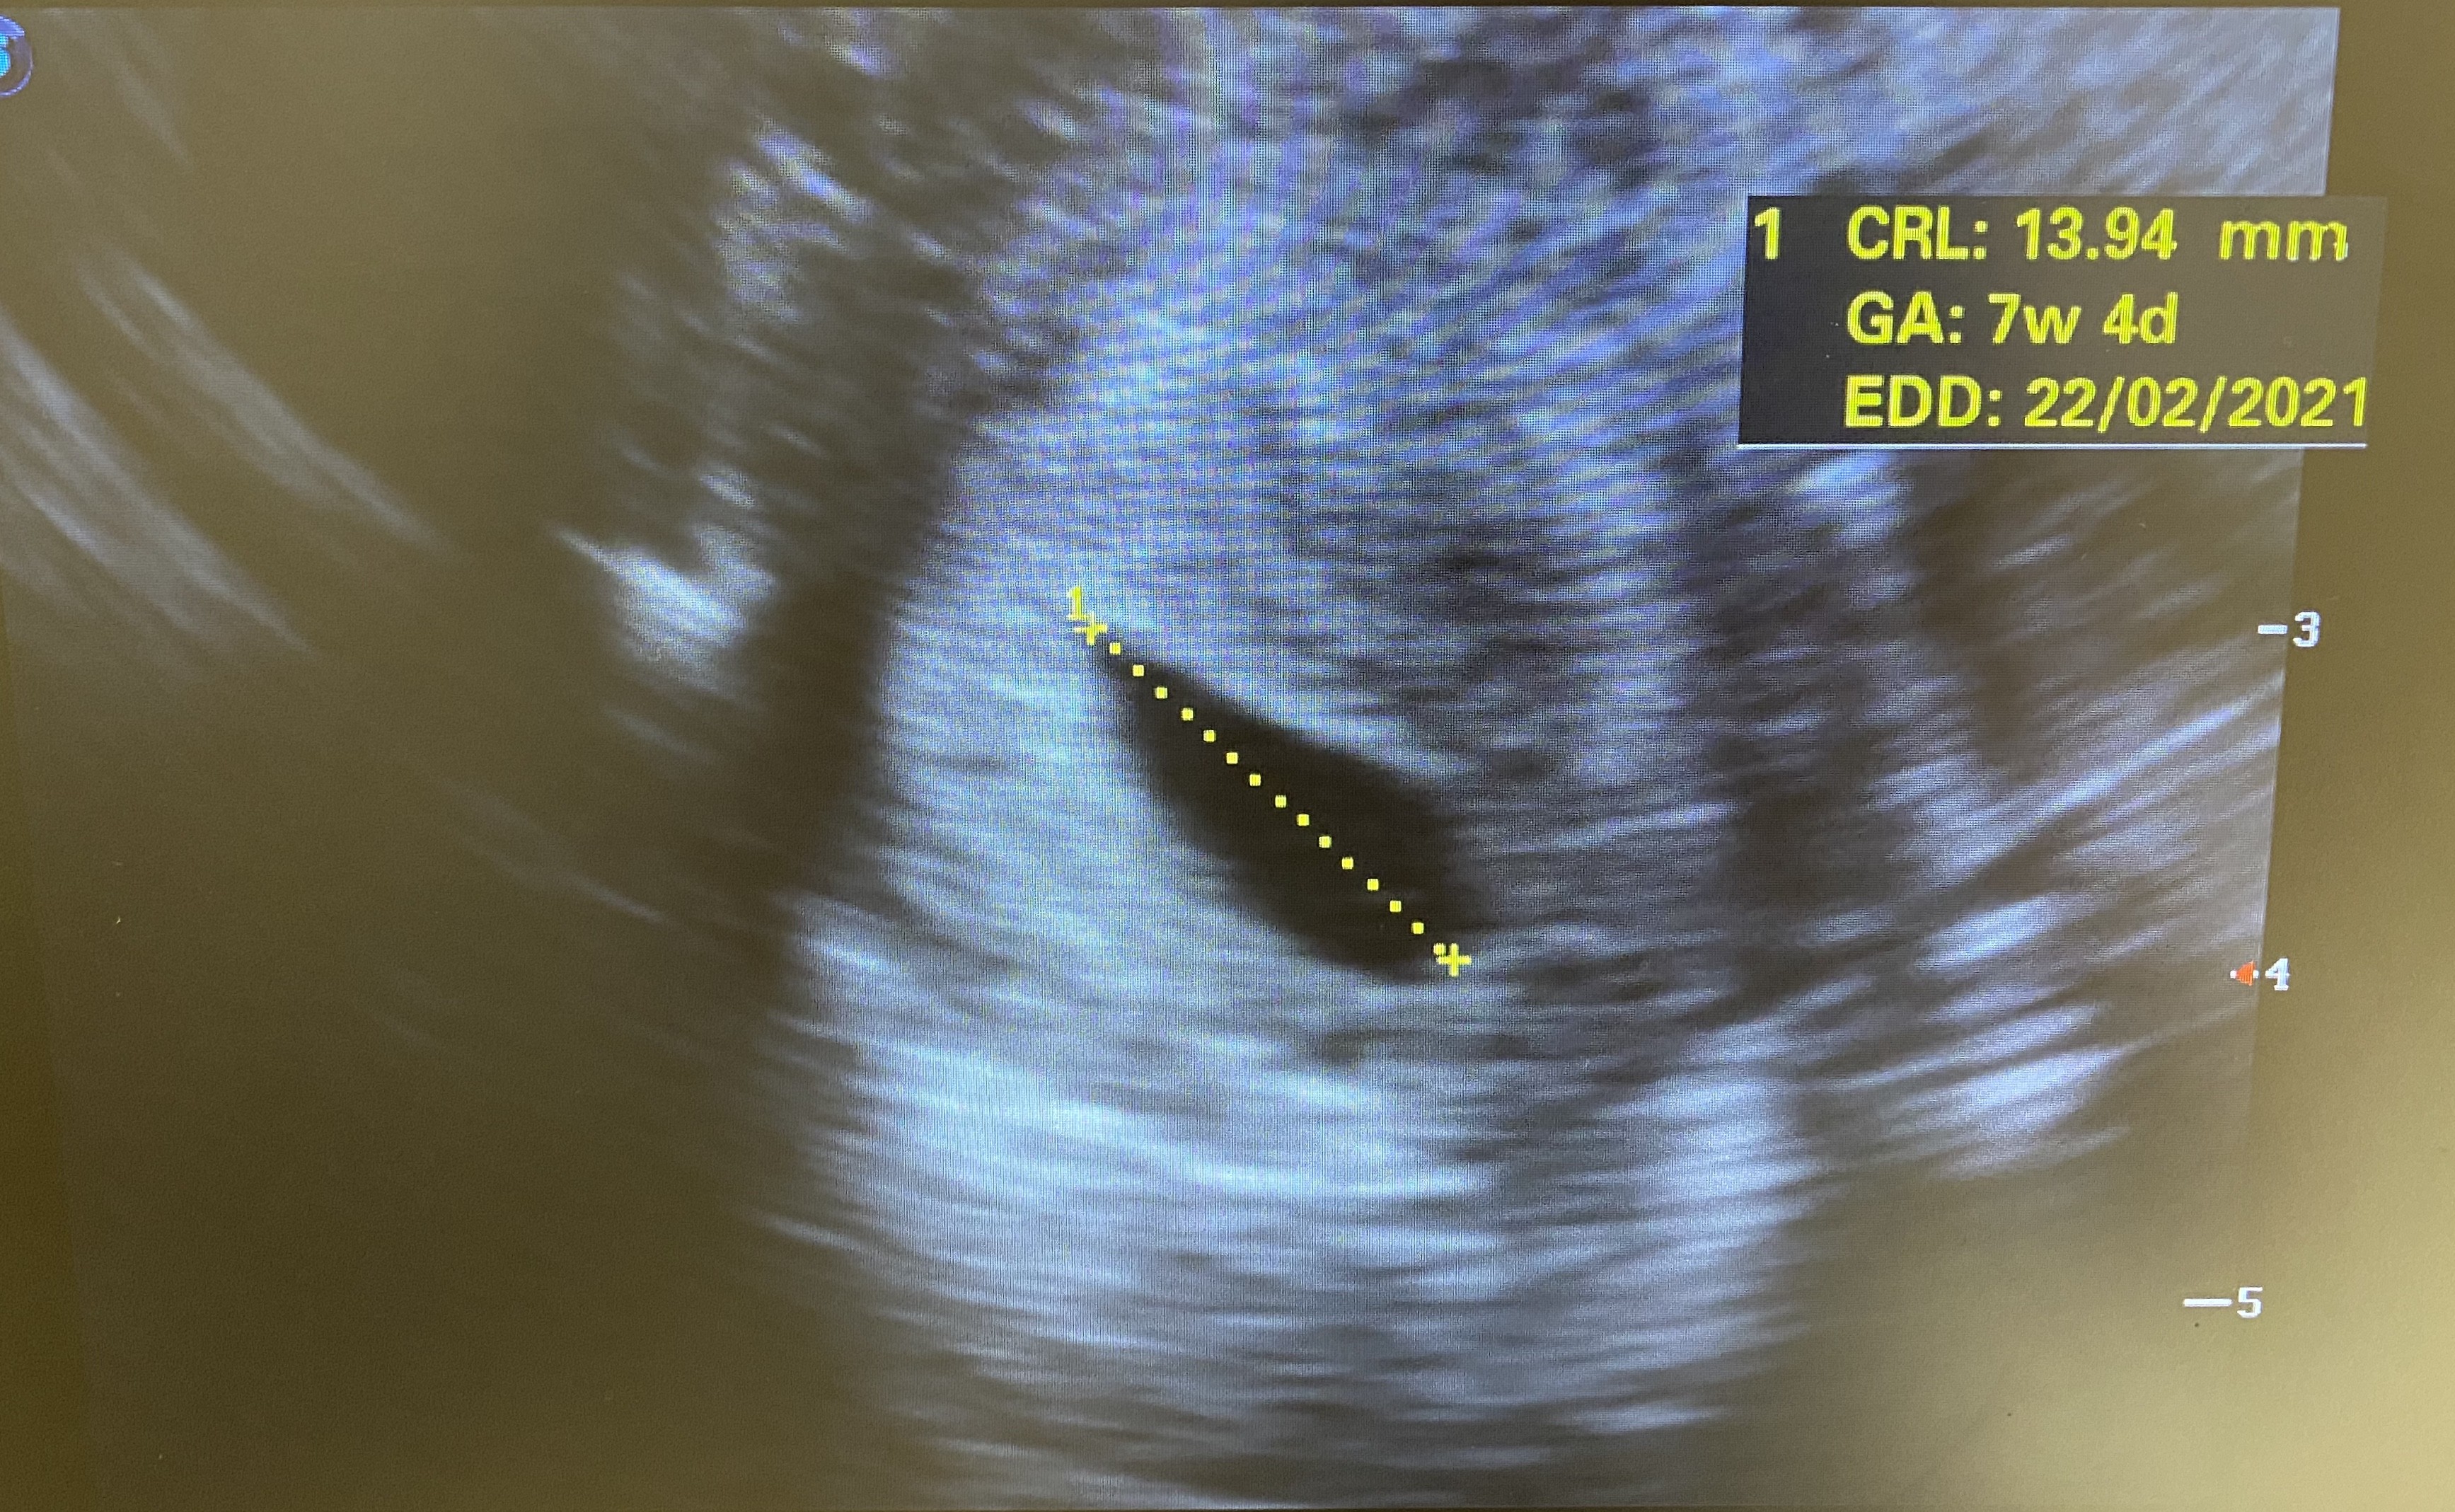

Jestes pewna? CRL to długość zarodka, tu pisze 13,94.

Do tego z usg wynika data poczęcia ok 27 maj.

Dziwne to bo niby piszesz brak zarodka a podana jego długość. Aczkolwiek na zdjeciu go nie widac.